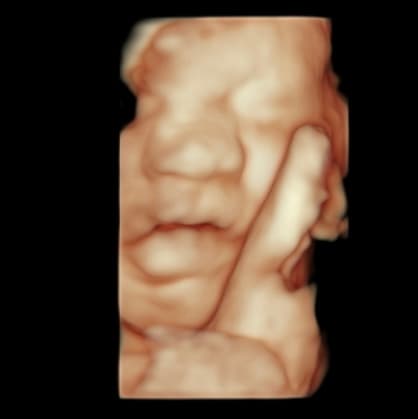

Explore our collection of ultrasound images and clinic photos. See the quality and clarity of our technology and the comfort of our facilities.

Book an appointment today and capture beautiful images of your baby. Our state-of-the-art technology provides clear, detailed ultrasound images for you to cherish forever.